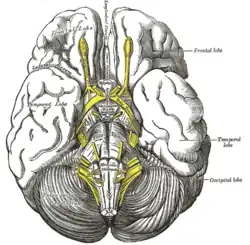

Base of brain.